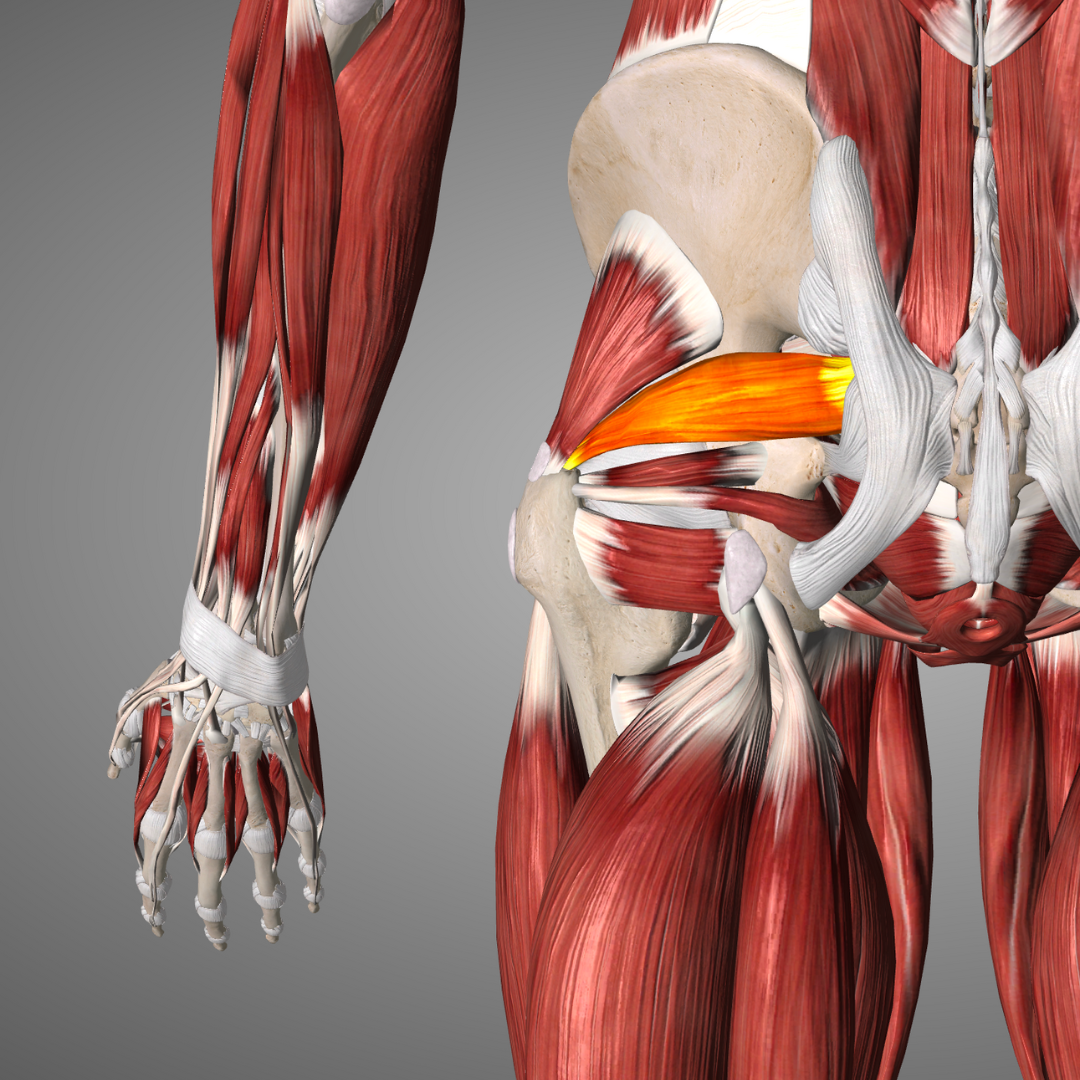

TENDINOPATÍA DE LA PATA DE GANSO

La tendinopatía de la pata de ganso es una lesión que afecta a los tendones ubicados en la parte interna de la rodilla. La terapia manual puede ser una estrategia eficaz para abordar esta condición. A través de técnicas como el masaje, la movilización articular y el estiramiento, se busca reducir la inflamación y promover la curación de los tendones, afectados. El terapeuta manual se enfocará en los tendones del músculo sartorio, recto interno y semitendinoso para aliviar la tensión y fortalecer la musculatura circundante.

En este taller hablaremos de la técnica de masaje terapéutico, comprenderemos las bases de la técnica y conoceremos los efectos que se buscan con su aplicación.

Montse Herrero (fisioterapeuta y PNIE) para Master-D Barcelona